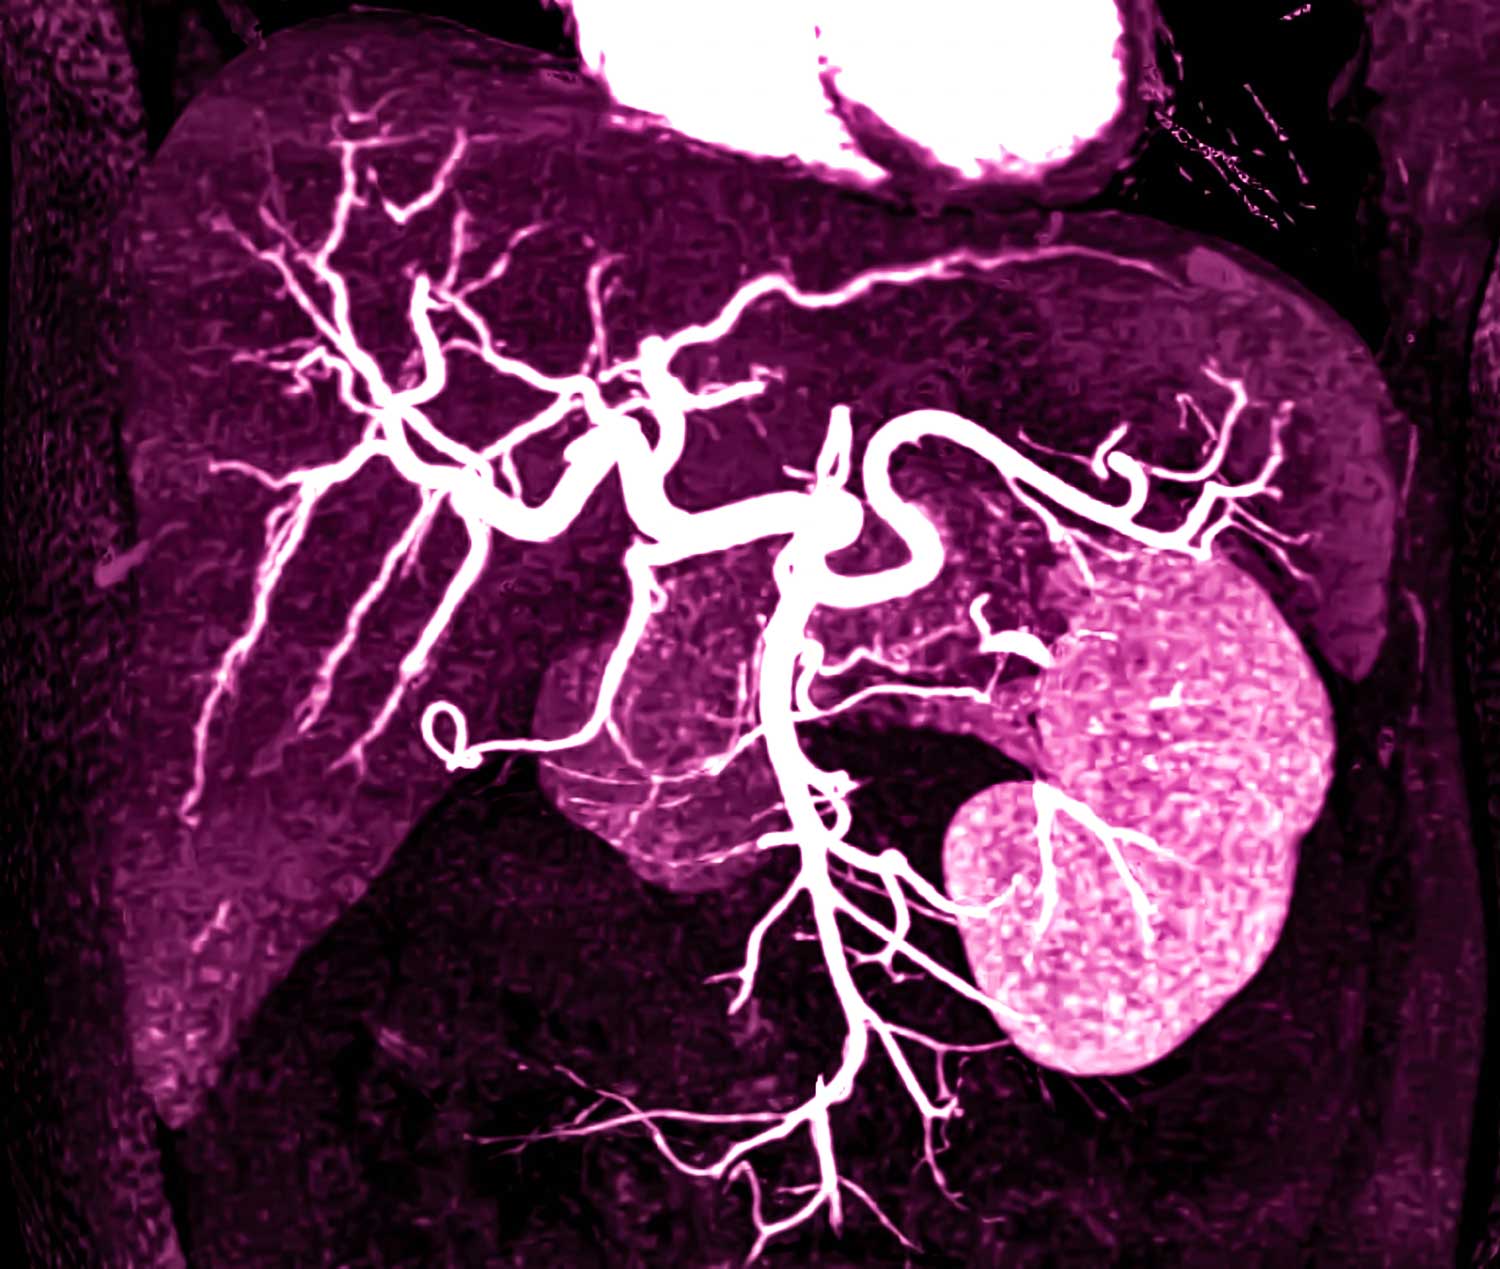

Die Diagnose kann sich sichern lassen, wenn sich eine arterielle Hypervaskularisation mit raschem Auswaschen des Kontrastmittels und relativer Kontrastumkehr zum umgebenden Leberparenchym bildgebend erkennen lässt. Außerdem sind radiologische Schnittbildgebungsverfahren bei unzureichender sonographischer Beurteilbarkeit heranzuziehen. Auf diese Art und Weise kann insbesondere bei Zirrhosepatienten die HCC-Diagnose anhand des typischen Kontrastmittelverhaltens rein bildgebend ohne Notwendigkeit einer histologischen Sicherung gestellt werden.